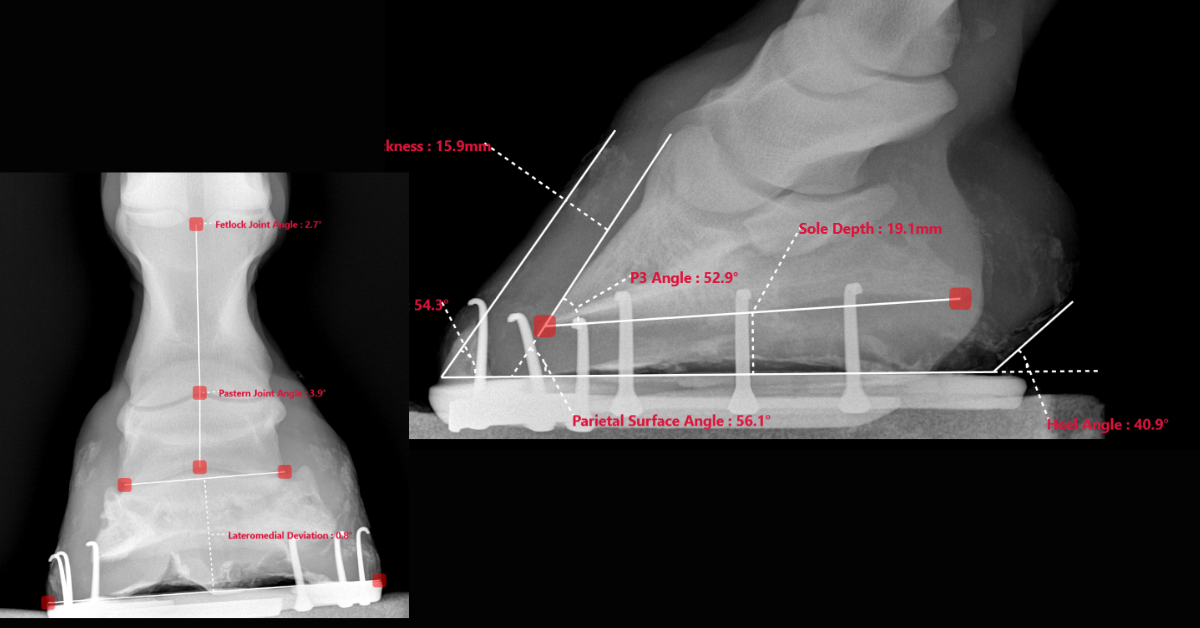

Samples of X-Rays